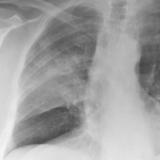

SCLC

Album: SCLC

Date: 10/01/2006

Size: 3 items

Views: 30525